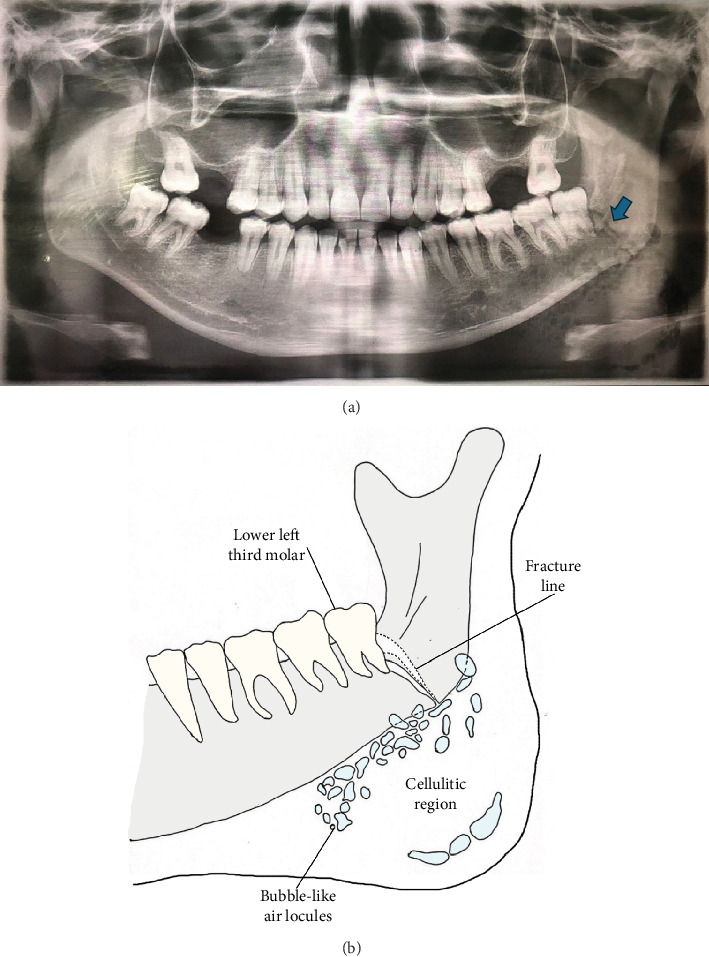

Facial cellulitis with palpable crepitus is a rare complication following a nondisplaced angle of mandible fracture. We report a case of a male in his mid-20s who presented with suspected emphysematous cellulitis of the face 3 days after an assault. Clinical examination revealed diffuse facial swelling with palpable subcutaneous crepitus over the left cheek and submandibular region. The patient had trismus and suppuration of the lower left third molar but no intraoral soft tissue injury. An orthopantomogram (OPG) showed a left nondisplaced angle of mandible fracture and multilocular bubble-like radiolucencies, suggesting submasseteric and submandibular gas accumulation. Due to financial constraints, advanced imaging and histological evaluation were not performed, limiting diagnostic certainty. Incision and drainage were performed, followed by intermaxillary fixation (IMF), and the infection was resolved with intravenous antibiotics. Open reduction internal fixation (ORIF) was not pursued due to cost limitations, but the fracture healed successfully within 6 weeks of IMF. This case underscores the importance of recognising gas-forming infections following mandibular trauma, the diagnostic challenges in resource-limited settings, and the role of early intervention in preventing severe complications.